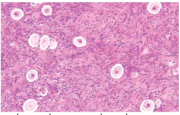

| 12:27, 3 במרץ 2015 | Irradiation4.png (קובץ) |  |

158 קילו־בייטים | Motyk | 1 | |

| 20:10, 2 במרץ 2015 | Irradiation3.png (קובץ) |  |

150 קילו־בייטים | Motyk | 1 | |

| 19:38, 2 במרץ 2015 | Irradiation2.png (קובץ) |  |

217 קילו־בייטים | Motyk | 1 | |

| 19:34, 2 במרץ 2015 | Irradiation1.png (קובץ) |  |

468 קילו־בייטים | Motyk | 1 | |